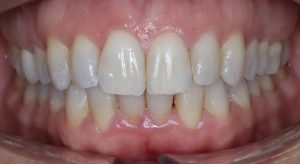

INITIAL

22 Semanas de Tratamiento